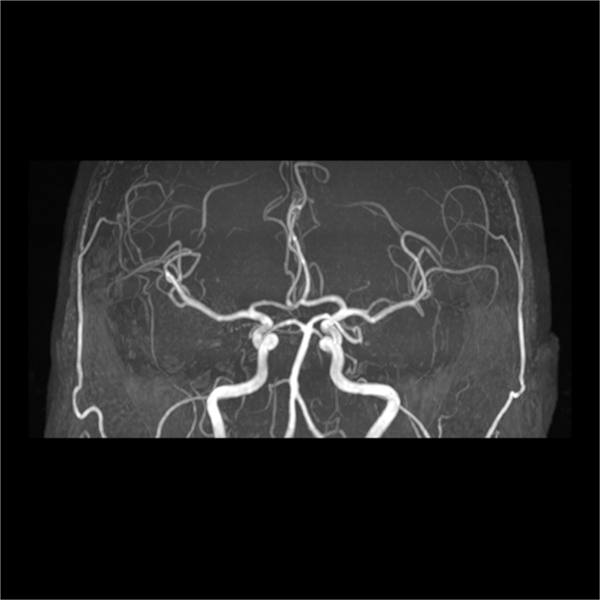

(五)血管成像:无需注射对比剂,对全身血管进行扫描,先进的多角度后处理重建,保证了扫描区域内血管的连续性。用于检查颅内、颈部以及四肢的动脉瘤、动静脉畸形、静脉病变等。

头颅血管与神经联合显示

血管成像图